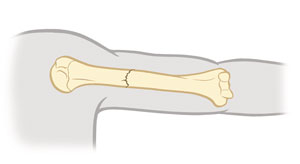

Fractura sin desplazamiento

Los fragmentos (partes) de hueso están alineados.